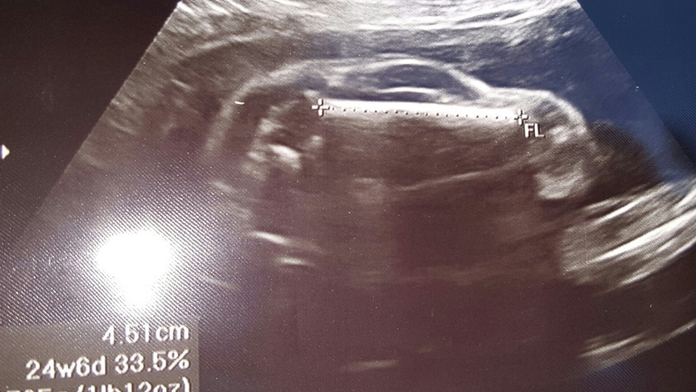

Muž bol po ultrazvuku v šoku. Týmto príspevkom pobúril internet

Mal to byť vtip, no málokto to pochopil. Muž absolvoval s tehotnou manželkou ultrazvuk. Po návšteve lekára ale ostal v šoku. Jeho bábätko bolo v brušku tak otočené, že na snímke vyzeralo ako malé športové auto. Snímku zverejnil na portál Reddit s vtipným komentárom: „Moja žena čaká športové auto."

My wife is pregnant with a sports car from mildlyinteresting